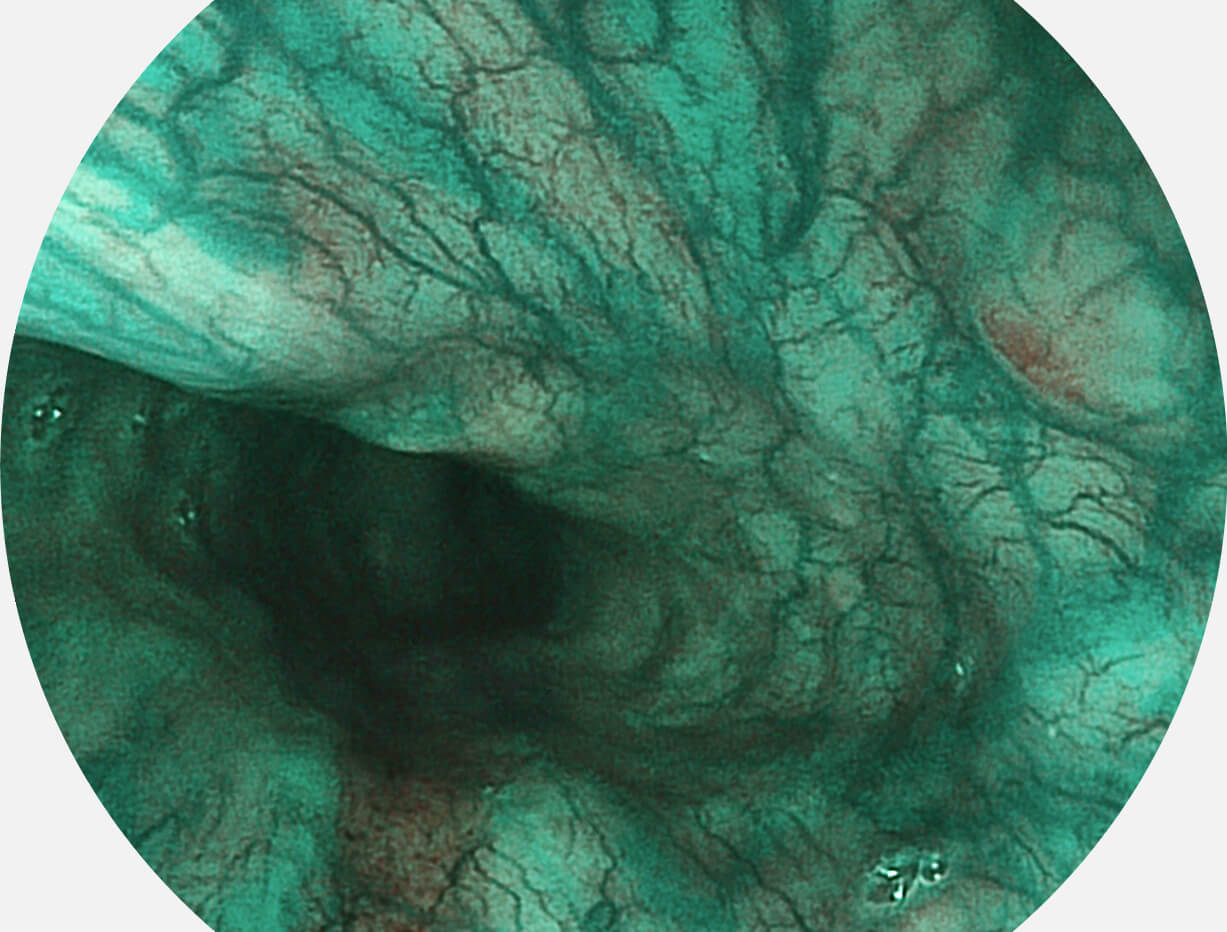

SFI图像

白光图像

Spectral Focused lmaging, SFI

图像具有高亮度、高黏膜血管颜色对比度的特点,且不改变粘液、食物残渣、粪便的基本颜色,可在中远景下进行观察,助力消化道早期疾病的诊断。